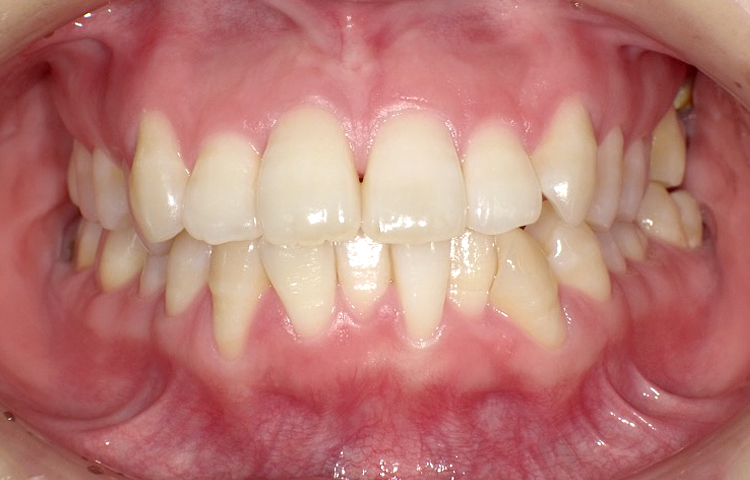

症例2

治療前

治療後

| 主訴 | 上の前歯のガタつきが気になるので前歯だけ綺麗にして欲しい |

|---|---|

| 治療 期間 |

約6ヶ月 |

| 治療費 | 165,000円(税込)/調整費用別途 |

| 治療 内容 |

上の前歯部にワイヤーを着けて進めていく、プチ矯正で施術。 |

| 治療の リスク |

見た目を綺麗にする目的で短期間で仕上げる為噛み合わせは矯正しない。 |